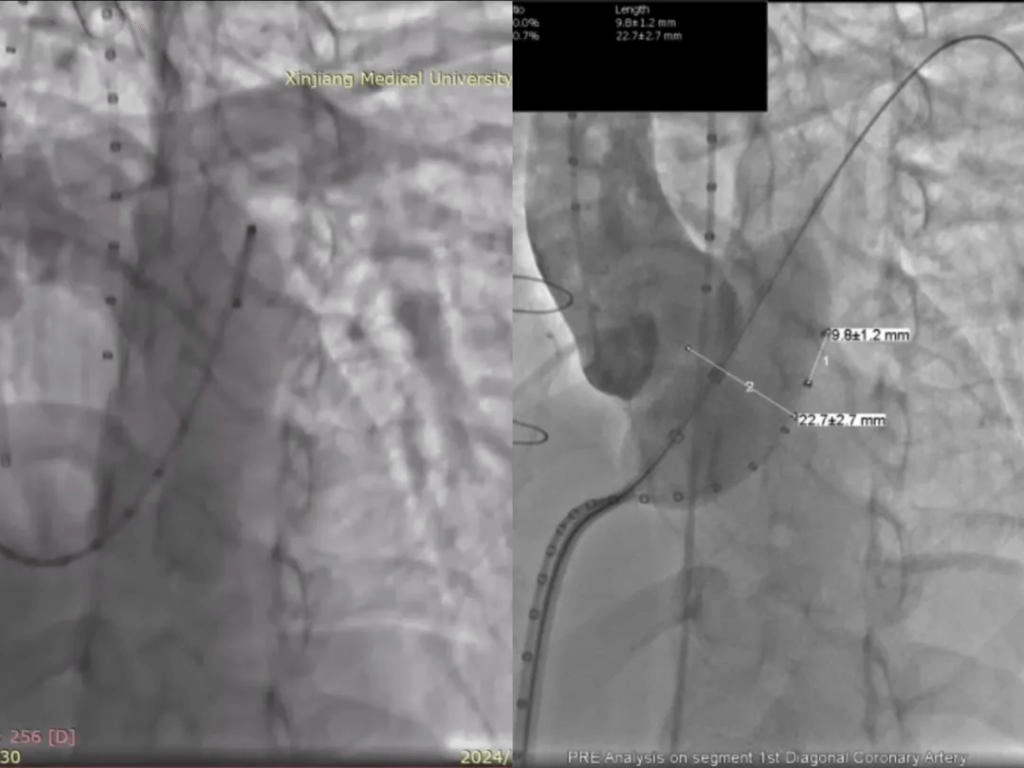

左图:肺动脉造影可见大量肺动脉瓣反流;

右图:充盈测径球囊,同时行冠脉造影;

术中,马翔主任医师、刘成副主任医师联合四川大学华西医院冯沅教授实施手术,术中造影可见大量肺动脉瓣反流,沿右股静脉—下腔静脉—右心房—右心室—肺动脉送入超硬导丝建立轨道。根据测径球囊的测量,选用P30-25型号的VenusP-Valve瓣膜,至肺动脉分叉处开始释放,释放完成后重复造影可见人工瓣膜位置准确,形态良好,未见明显肺动脉瓣反流及瓣周漏。术后即刻拔除气管插管,手术成功。